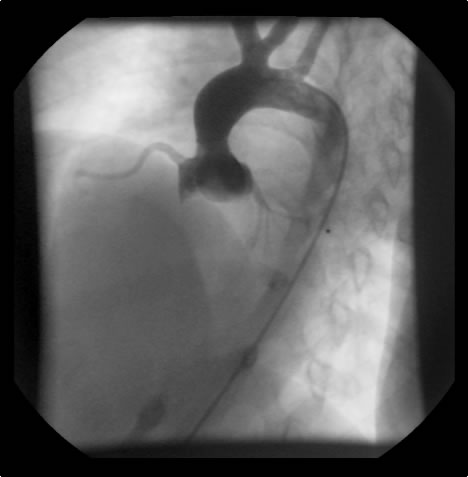

Brom’s three-patch aortoplasty is indicated for the repair of supravalvar aortic stenosis, which can occur as an isolated defect or as a part of Williams syndrom [1]. This syndrome is characterized by supravalvar aortic stenosis, elfin craniofacial features, peripheral pulmonary artery stenosis, and hypercalcemia. The underlying cause is a loss of function mutation of the elastin gene on chromosome 7q11.23. These patients will have a systolic cardiac murmur and two-dimensional echocardiography can establish the diagnosis. Cardiac catheterization is indicated to evaluate the status of the coronary arteries and assess the pulmonary arterial tree for related peripheral stenosis.

Indications for surgery include symptoms of diminished exercise tolerance, syncope, or angina. Other indications would include 1) systolic ascending aorta gradient greater than 50 mm Hg, 2) aortic valve insufficiency, or 3) evidence of compromised coronary artery perfusion. These patients should undergo surgery at a relatively early age because of the detrimental effect of the high proximal aortic pressure on the coronary arteries with the possibility for accelerated atherosclerotic changes. These patients typically have a thickening of the aortic wall at the sinotubular junction. This abnormal thickening may extend into the ascending aorta and even into the aortic arch. In some patients, this abnormal thickening creates stenosis of the coronary ostium.

An asymptomatic, 5-year-old, 18-kg boy known by genetic testing to have Williams syndrome on physical examination had a IV/VI harsh systolic ejection murmur and no diastolic murmur. Preoperative echocardiogram showed an aortic root dimension of 2 cm and the dimension at the level of stenosis in the ascending aorta was 8 mm. Peak echocardiogram gradient was 70 mm Hg with a cardiac catheterization gradient of 50 mm Hg. The child had no peripheral pulmonary artery stenosis.